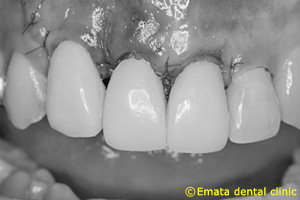

縫合時です。糸7-0でおこなうので傷口は全くわかりません。